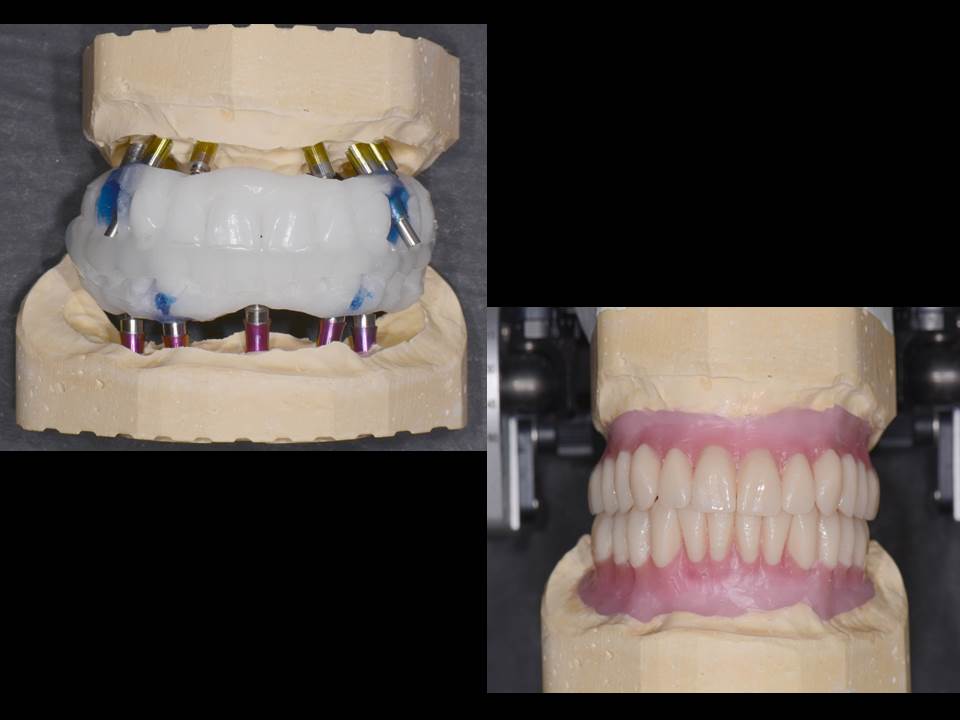

Prótesis fija OT BRIDGE

OT Equator Biologic Abutment